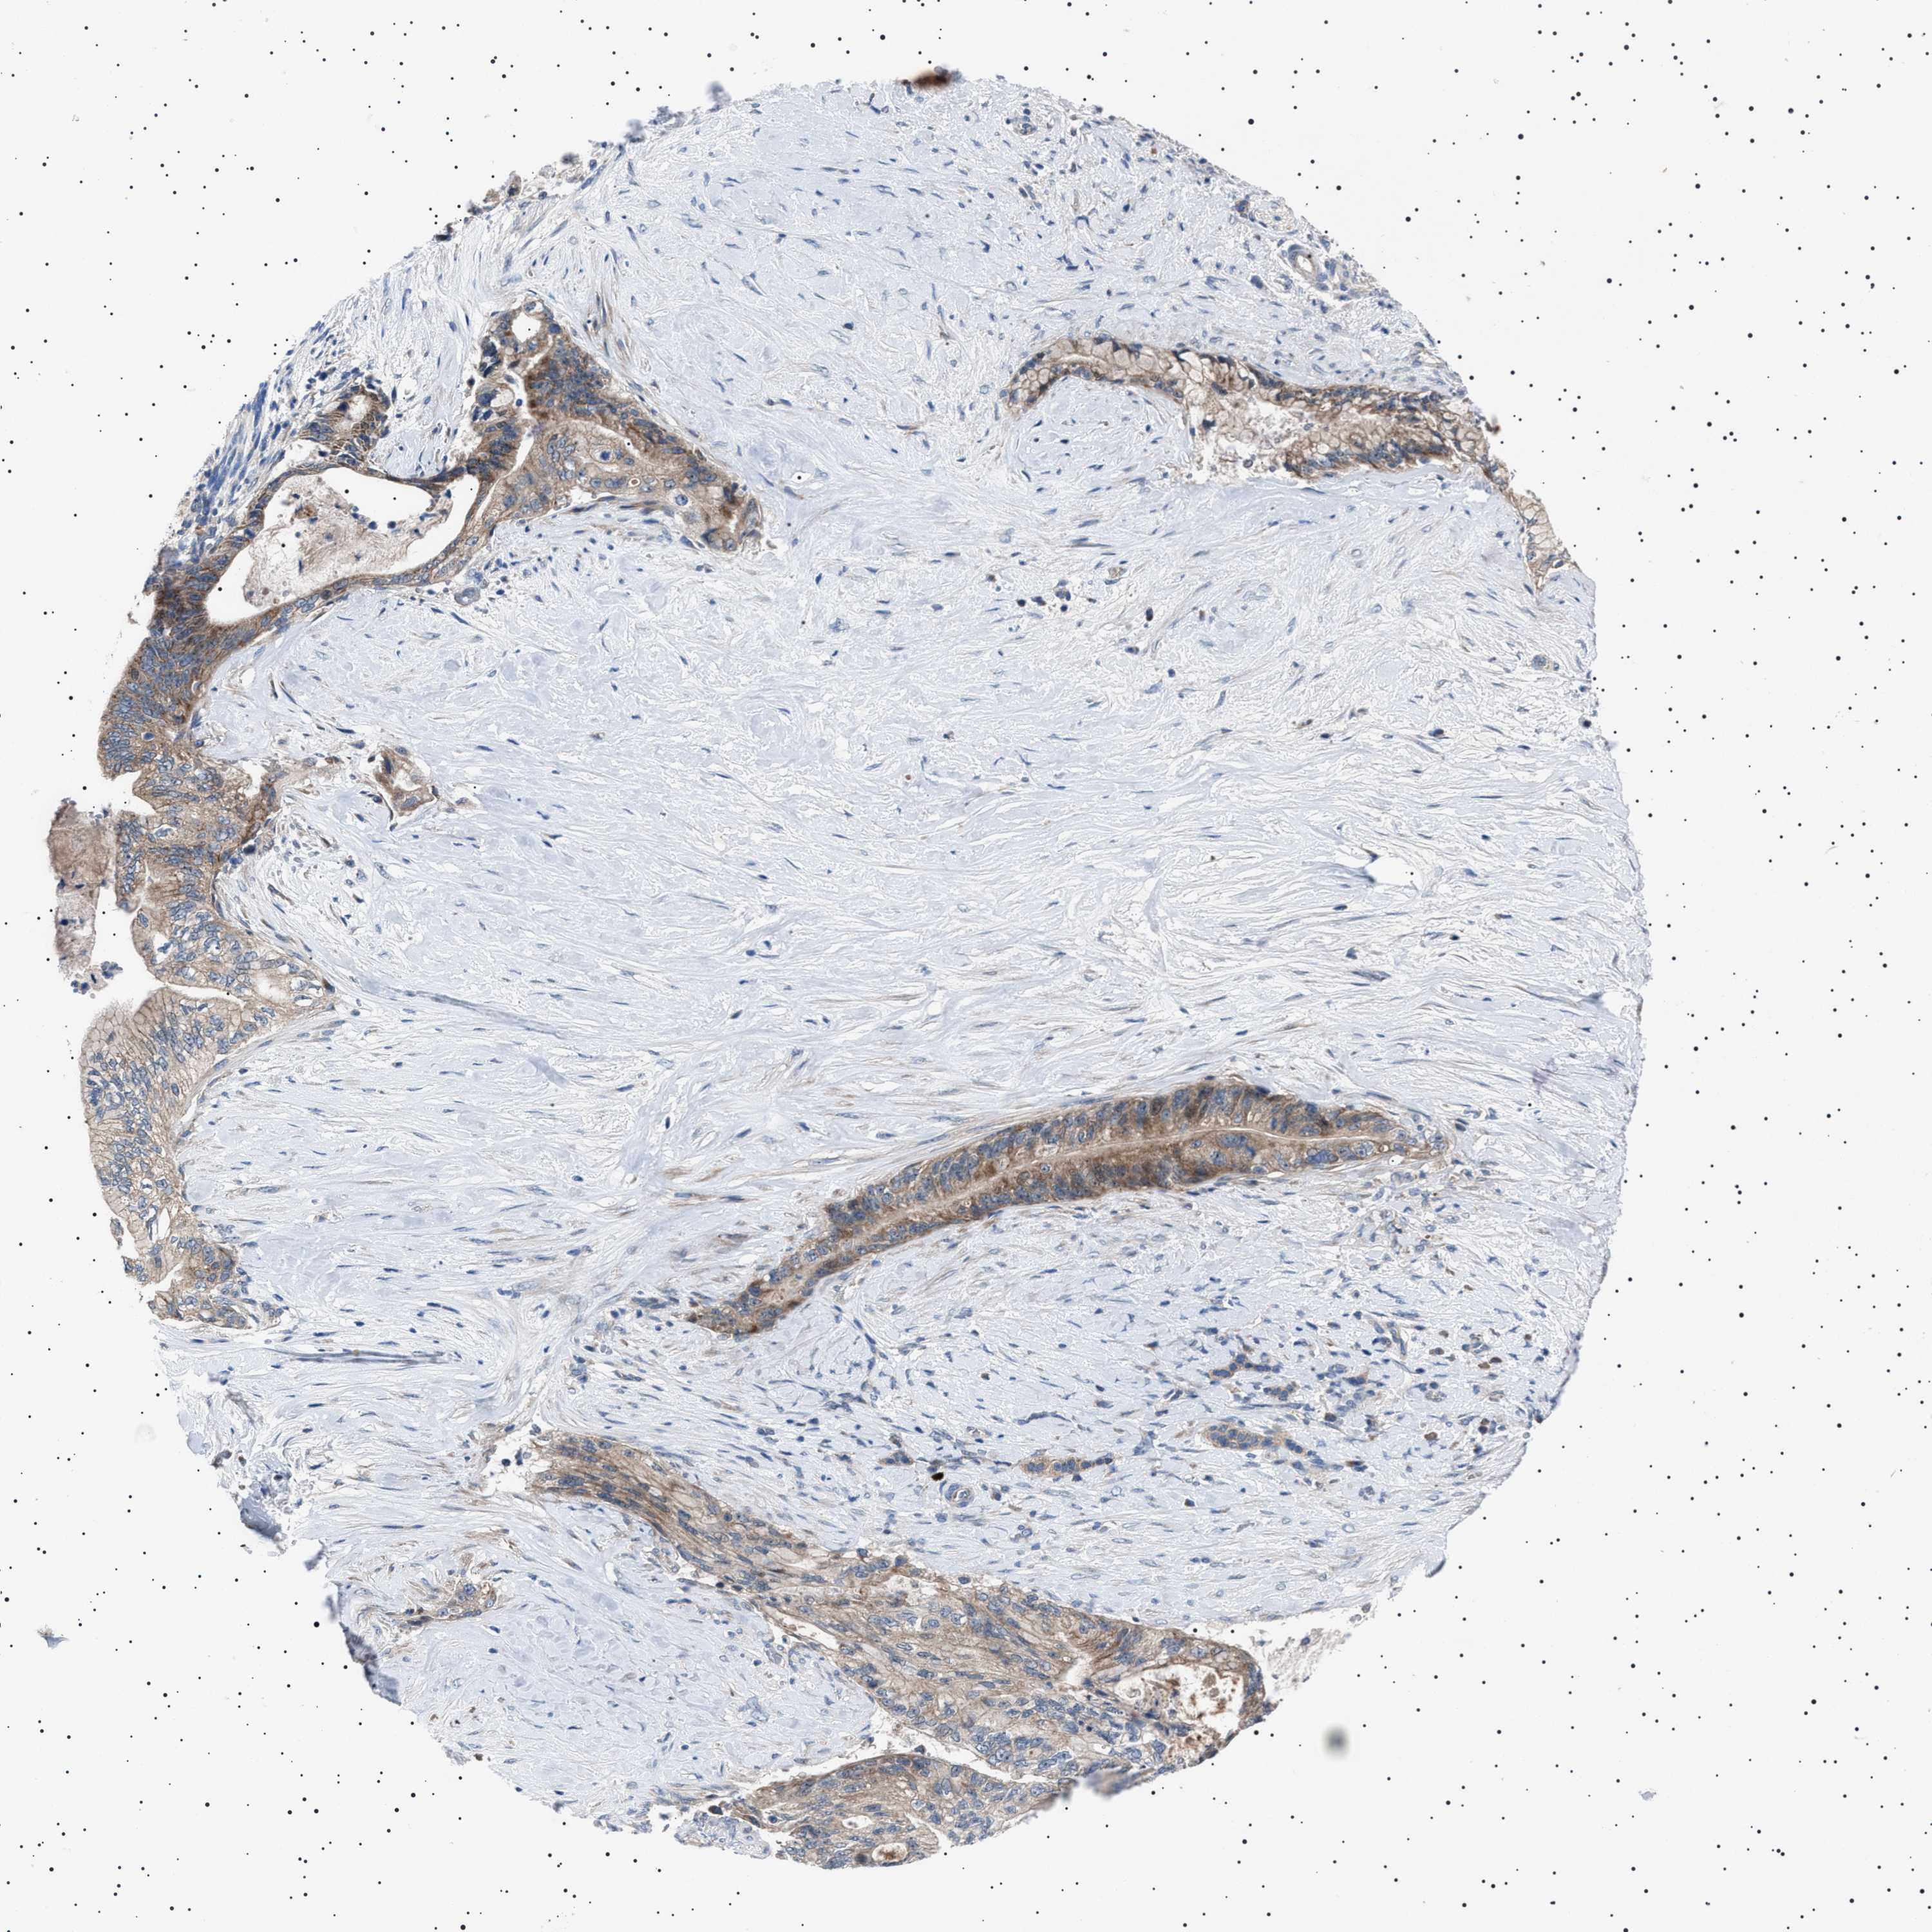

PANCREATIC CANCER - Protein expressioni

A mouse-over function shows sample information and annotation data. Click on an image to view it in a full screen mode. Samples can be filtered based on level of antibody staining by selecting one or several of the following categories: high, medium, low and not detected. The assay and annotation is described here.

Note that samples used for immunohistochemistry by the Human Protein Atlas do not correspond to samples in the TCGA dataset.

Antibody stainingi

Antibody staining in the annotated cell types in the current human tissue is reported as not detected, low, medium, or high, based on conventional immunohistochemistry profiling in selected tissues. This score is based on the combination of the staining intensity and fraction of stained cells.

Each image is clickable and will lead to virtual microscopy that enables deeper exploration of all samples and also displays staining intensity scores, fraction scores and subcellular localization as well as patient and tissue information for each sample.

Antibody HPA021223

Staining

High

Medium

Low

Not detected

Intensity

Strong

Moderate

Weak

Negative

Quantity

>75%

75%-25%

<25%

None

Location

Nuclear

Cytoplasmic/membranous

Cytoplasmic/membranous,nuclear

Adenocarcinoma, NOS